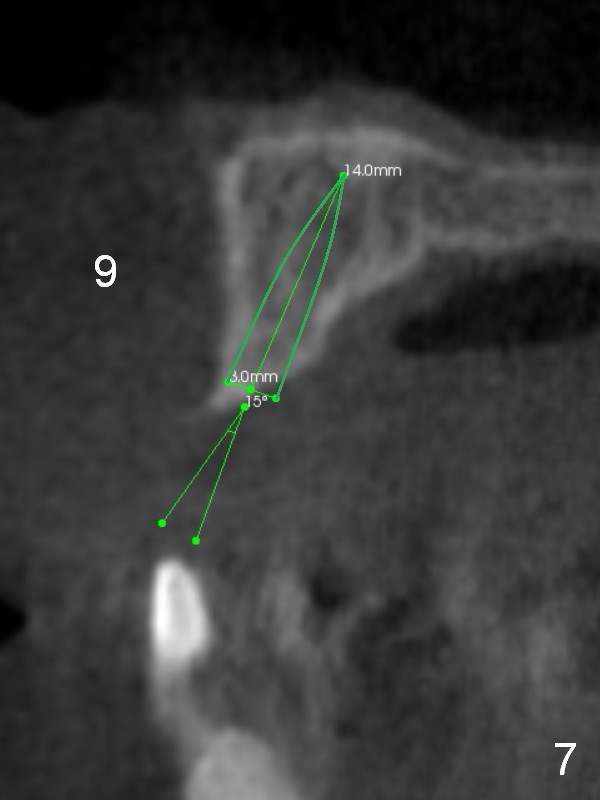

After implant reconstruction of the lower right and left (including #19) regions, the same treatment is considered in the atrophic anterior maxilla (#8-13) for anchorage for upper left molar cross bite correction. The smallest implants are to be placed in the each of the sites with different strategies. For example, at the site of #8 (Fig,1,2), ridge split with wheel (Fig.3) and microsteotomes (Fig.4) are used to place 1-piece implant (3x14 mm). The site of #9 has a pointed ridge and a wide base (Fig.6); a 1-piece angled implant (3x14 mm 15 °) is placed palatally (Fig.7). The ridge and base at #10 are narrow (Fig.8); after truncating the pointed ridge, a 2.0 or 2.5 mm 1-piece implant is placed parallel to the palatal wall (Fig.9).